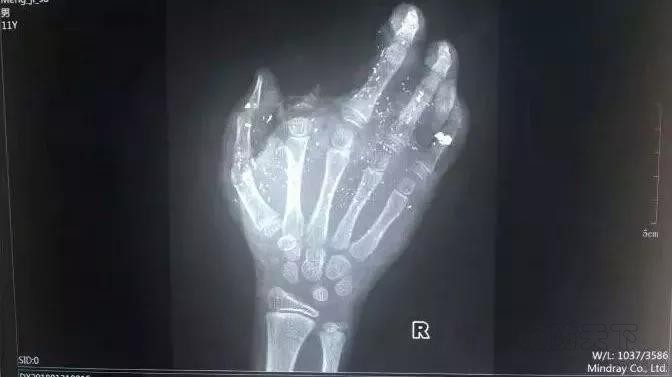

2.手機充電爆炸,男孩斷指

2018年1月31日上午,廣西發生一起手機爆炸事件,一名年僅12歲的小男孩手掌被炸得血肉模糊,其中一個斷指無法再接!